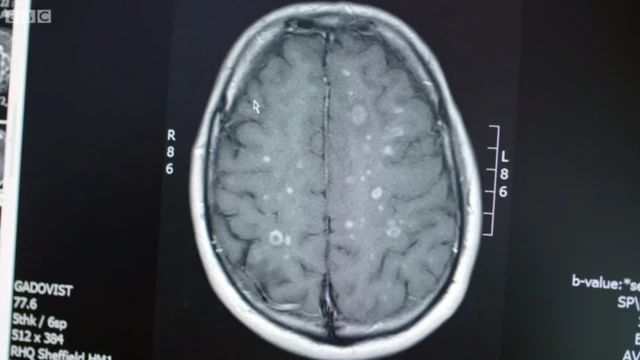

La BBC lo acompañó en una de esas revisiones, en la que los neurólogos compararon un escáner cerebral tomado antes del tratamiento con otro actual.

"Los puntos blancos en el escáner previo al tratamiento son zonas donde hay inflamación activa", explicó el profesor Sharrack.

El neurólogo le mostró a Stephen cómo en las imágenes anteriores al tratamiento había muchos de esos puntos y afectaban a todo su cerebro.

Pero en el actual no había ninguna.

"Esto es muy gratificante", dijo el neurólogo.

"Estoy impresionado, es fenomenal", dijo Stephen, emocionado.